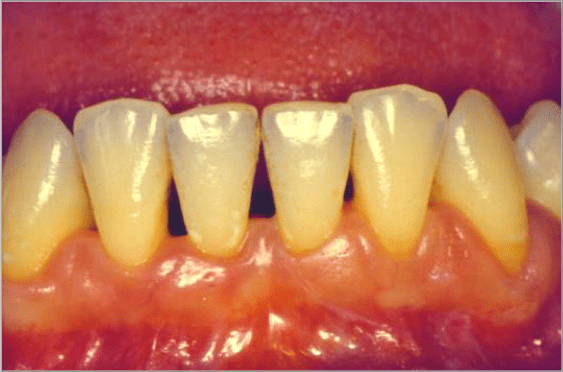

Recessione gengivale in paziente adulto

BlogGengive

Recessione gengivale

Read More